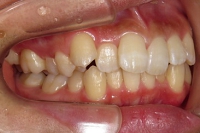

CASE4

前歯で物が噛み切れない。 顔が曲がって見える。

右のアゴが たまに痛い。

(19歳/女性)↓

概要・担当医コメント:

開咬/下顎の左右的偏位/顎関節症/非抜歯

動的治療期間28ヶ月(28回)/費用概算:65万円

顎関節症の改善を主目的として治療を開始しました.歯科矯正用アンカースクリューを使用することにより,上下とも非抜歯で治療出来ました.大臼歯の上下的位置を調整することで,顎関節に負担のかかり過ぎない噛み合わせにしました.